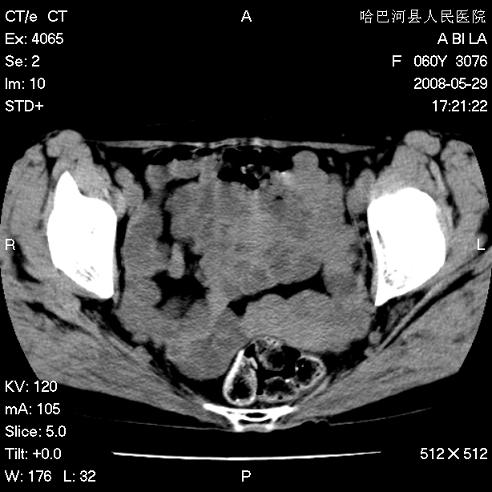

标题: CT13730:排尿不畅4天,抗炎治疗无效,现尿中可见血块 [打印本页]

标题: CT13730:排尿不畅4天,抗炎治疗无效,现尿中可见血块

膀胱内多发恶性占位,癌可能性大

手术结果及病理:膀胱癌并膀胱壁转移,膀胱内血块